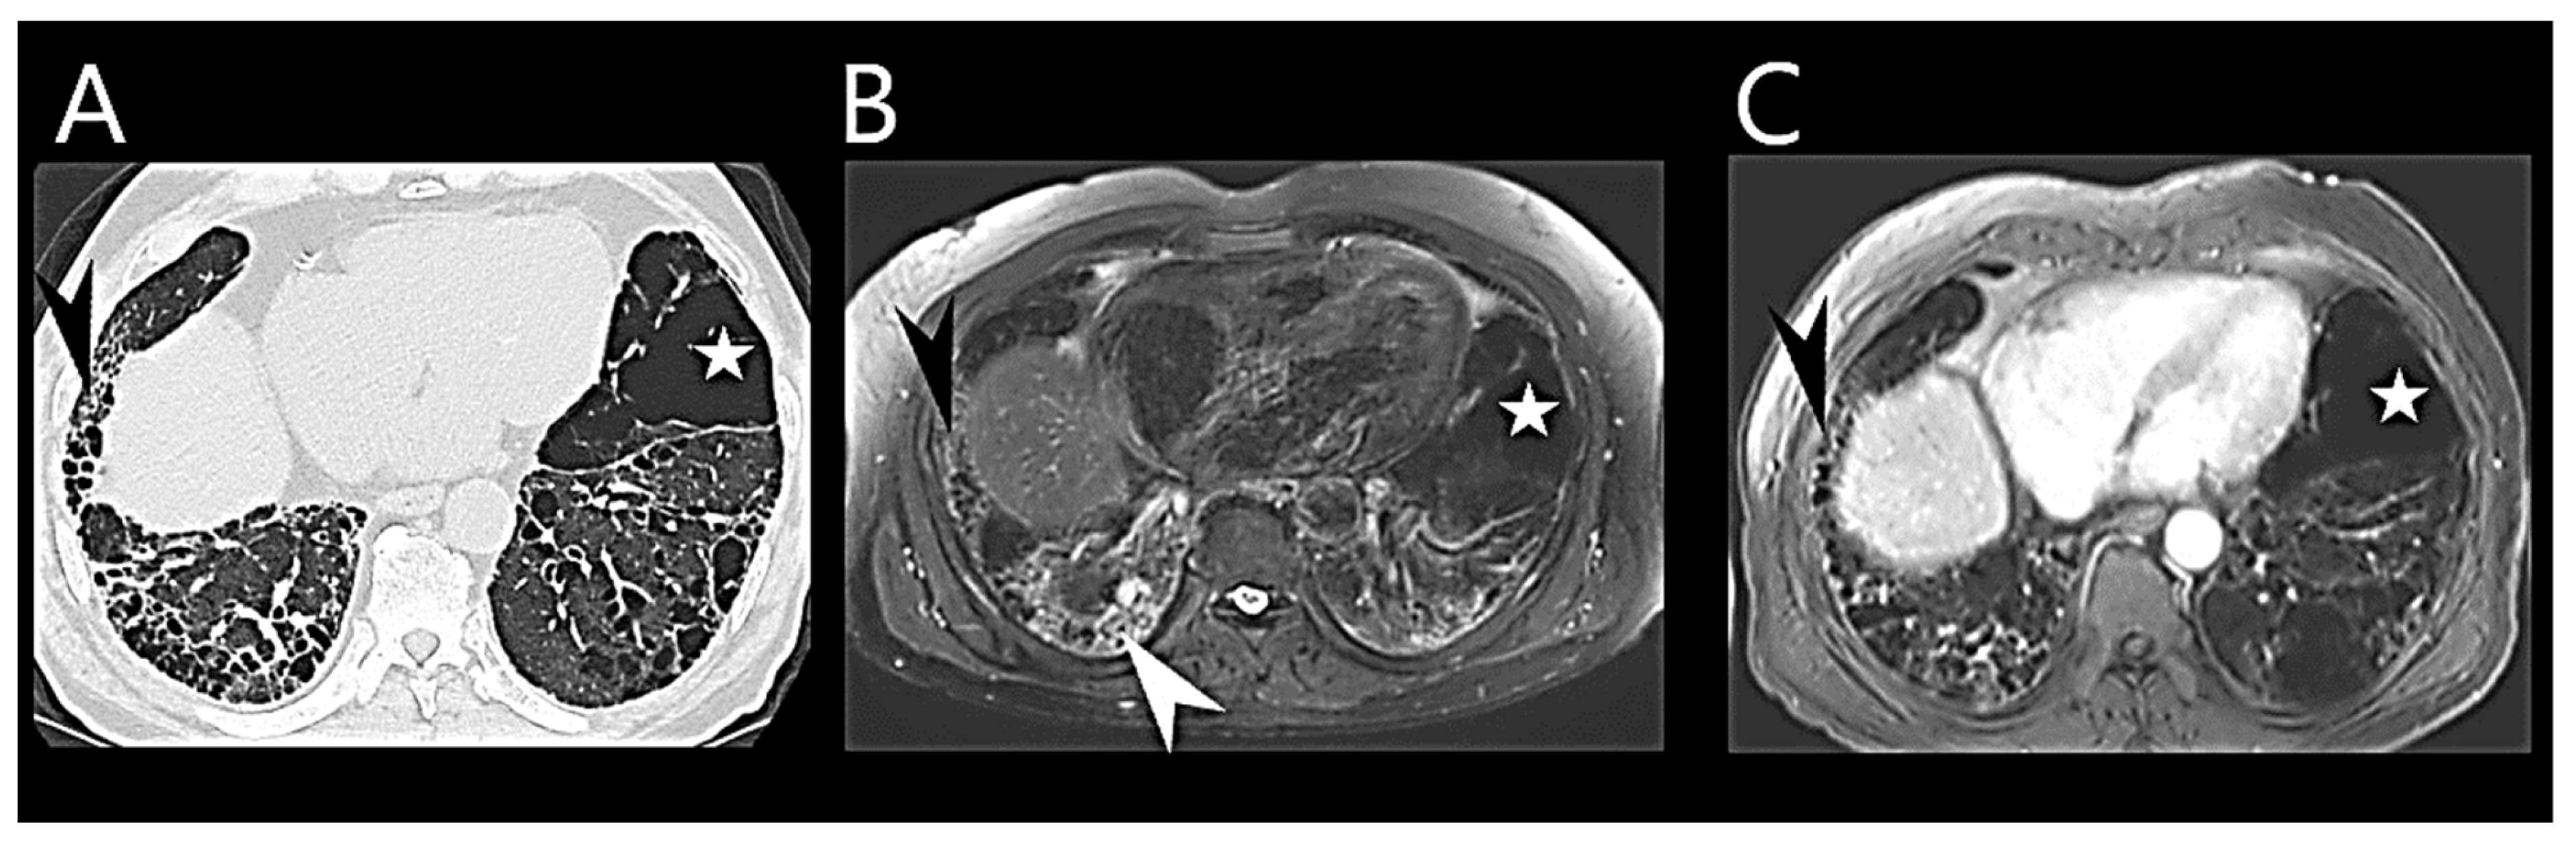

Various MRI parameters, including interventricular septal bowing, LV eccentricity, ventricular mass index, asynchrony, RV ejection fraction, and RV end-systolic volume index, have been utilized to evaluate overall hemodynamic condition and aid in PH diagnostics (Figure 3) [75,76,77,78].

Figure 3.

Cardiovascular magnetic resonance imaging in pulmonary hypertension. (A) End-diastolic 4-chamber view of a patient with pulmonary hypertension. There is dilation of the right ventricle (black star) and atrium (white star), with leftward septal bowing and hypertrophy of the right ventricular free wall and trabeculations. (B) Short-axis slice of the same patient. A stack of short-axis slices enables the quantification of volumes and mass. There is leftward septal bowing and hypertrophy of the right ventricular free wall and trabeculations (white arrow). (C) Pulmonary trunk in relation to the aorta. The pulmonary trunk and the right pulmonary artery are dilated.

Multivariate MRI models have been developed to accurately estimate PAP and differentiate disease severities in suspected PH patients [82,83]. Some models designed for identifying PH in chronic lung disease patients rely on parameters such as interventricular septal angle, ventricular mass index, and diastolic pulmonary artery area [84,85]. There are multiple novel and evolving MRI imaging approaches that report on the RV and might prove invaluable for earlier non-invasive PH diagnosis [86]. Recently, MRI has been emerging as an imaging modality to assess ILD (Figure 4).

Figure 4.

Cardiovascular magnetic resonance imaging (MRI) in idiopathic pulmonary fibrosis. Comparison of radiological findings in idiopathic pulmonary fibrosis with thin-slices multi-detector computed tomography (MDCT) and MRI. Thin-slices MDCT (A), MRI STIR (Shot Tau Inversion Recovery) sequence (B), and T1-weighted contrast-enhanced administration (at 10 min.) (C). The magnified images of MDCT and MRI show reticulation and honeycombing (black arrow) as well as areas of emphysema (white star). The high signal of ground-glass opacity in MRI (white arrow, (B)) may be due to water content and indicates active inflammation (white arrow, (B)).